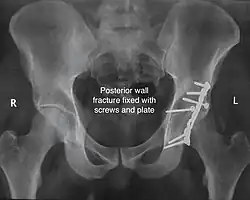

The final management depends on the size of the fragment(s), stability and congruence of the joint. In some cases traction for six to eight weeks may be the only treatment required; however, surgical fixation using screw(s) and plate(s) may be required if the injury is more complex. The latter treatment will be called for if bone fragments do not fall into place, or if they are found in the joint, or if the joint itself is unstable.

Innominate bone is a flat bone with many curves. In most part the bone is thick enough and has broad surfaces that are amenable to primary fixation using lag screw(s) and to neutralize forces across the bone one needs to add plate(s) on the surface of the fractured fragments for it to heal without deformity.

Implants : normally lag screws and reconstruction plates are preferred implants